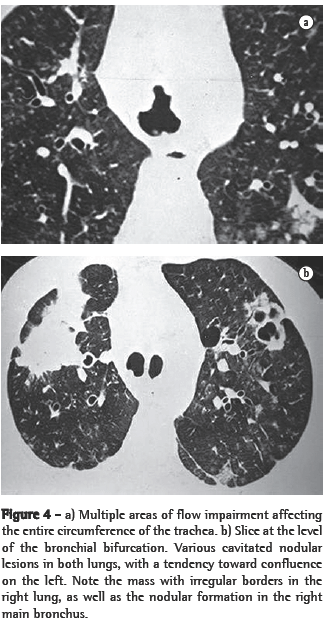

ResultsIn all eight cases, the CT scans revealed polypoid formations in the trachea. In one case, injury to one of the main bronchi was identified. Seven patients presented involvement of the pulmonary parenchyma. In all eight cases, there were cavitated polypoid lesions, with irregular internal borders and walls of various thicknesses, multilobulated in six cases and presenting confluence of the lesions in five (Figures 1 through 5). Solid nodules were seen in six patients. An air-fluid level was observed in only one patient. The lesions were predominantly in the lung bases in three patients and in the middle thirds in two, whereas they were evenly distributed in two. In one patient, the lesions were accompanied by a mass, and, in another patient, they were accompanied by consolidation. In the latter case (Figure 5), there was malignant degeneration in multiple lesions. Signs of air trapping were also observed in one case. There were no identified instances of lymph node enlargement or pleural effusion.

Chest X-rays are inferior to CT scans of the chest, especially those performed using spiral CT (volumetric acquisition), in the initial phases of pulmonary dissemination, due to the fact that CT better characterizes and allows better visualization of nodular tracheobronchial vegetation, Tomographic findings include focal or diffuse airway narrowing caused by the nodules. The nodules form on the mucosal surface, and their invasion into the lumen is best evaluated using CT.(3) These alterations are easily correlated with the disease when there is a clinical history of papillomatosis.(4) Other findings related to airway obstruction and accompanying infections are atelectasis, consolidations, air trapping and bronchiectasis.(2-4) In our sample, polypoid formations in the trachea were observed on all of the CT scans Seven patients presented involvement of the pulmonary parenchyma, characterized by cavitated polypoid lesions with irregular internal borders and walls of various thicknesses, with a multilobulated aspect and a tendency toward confluence. Solid nodules were seen in six patients. None of the patients presented lymph node enlargement or pleural effusion.